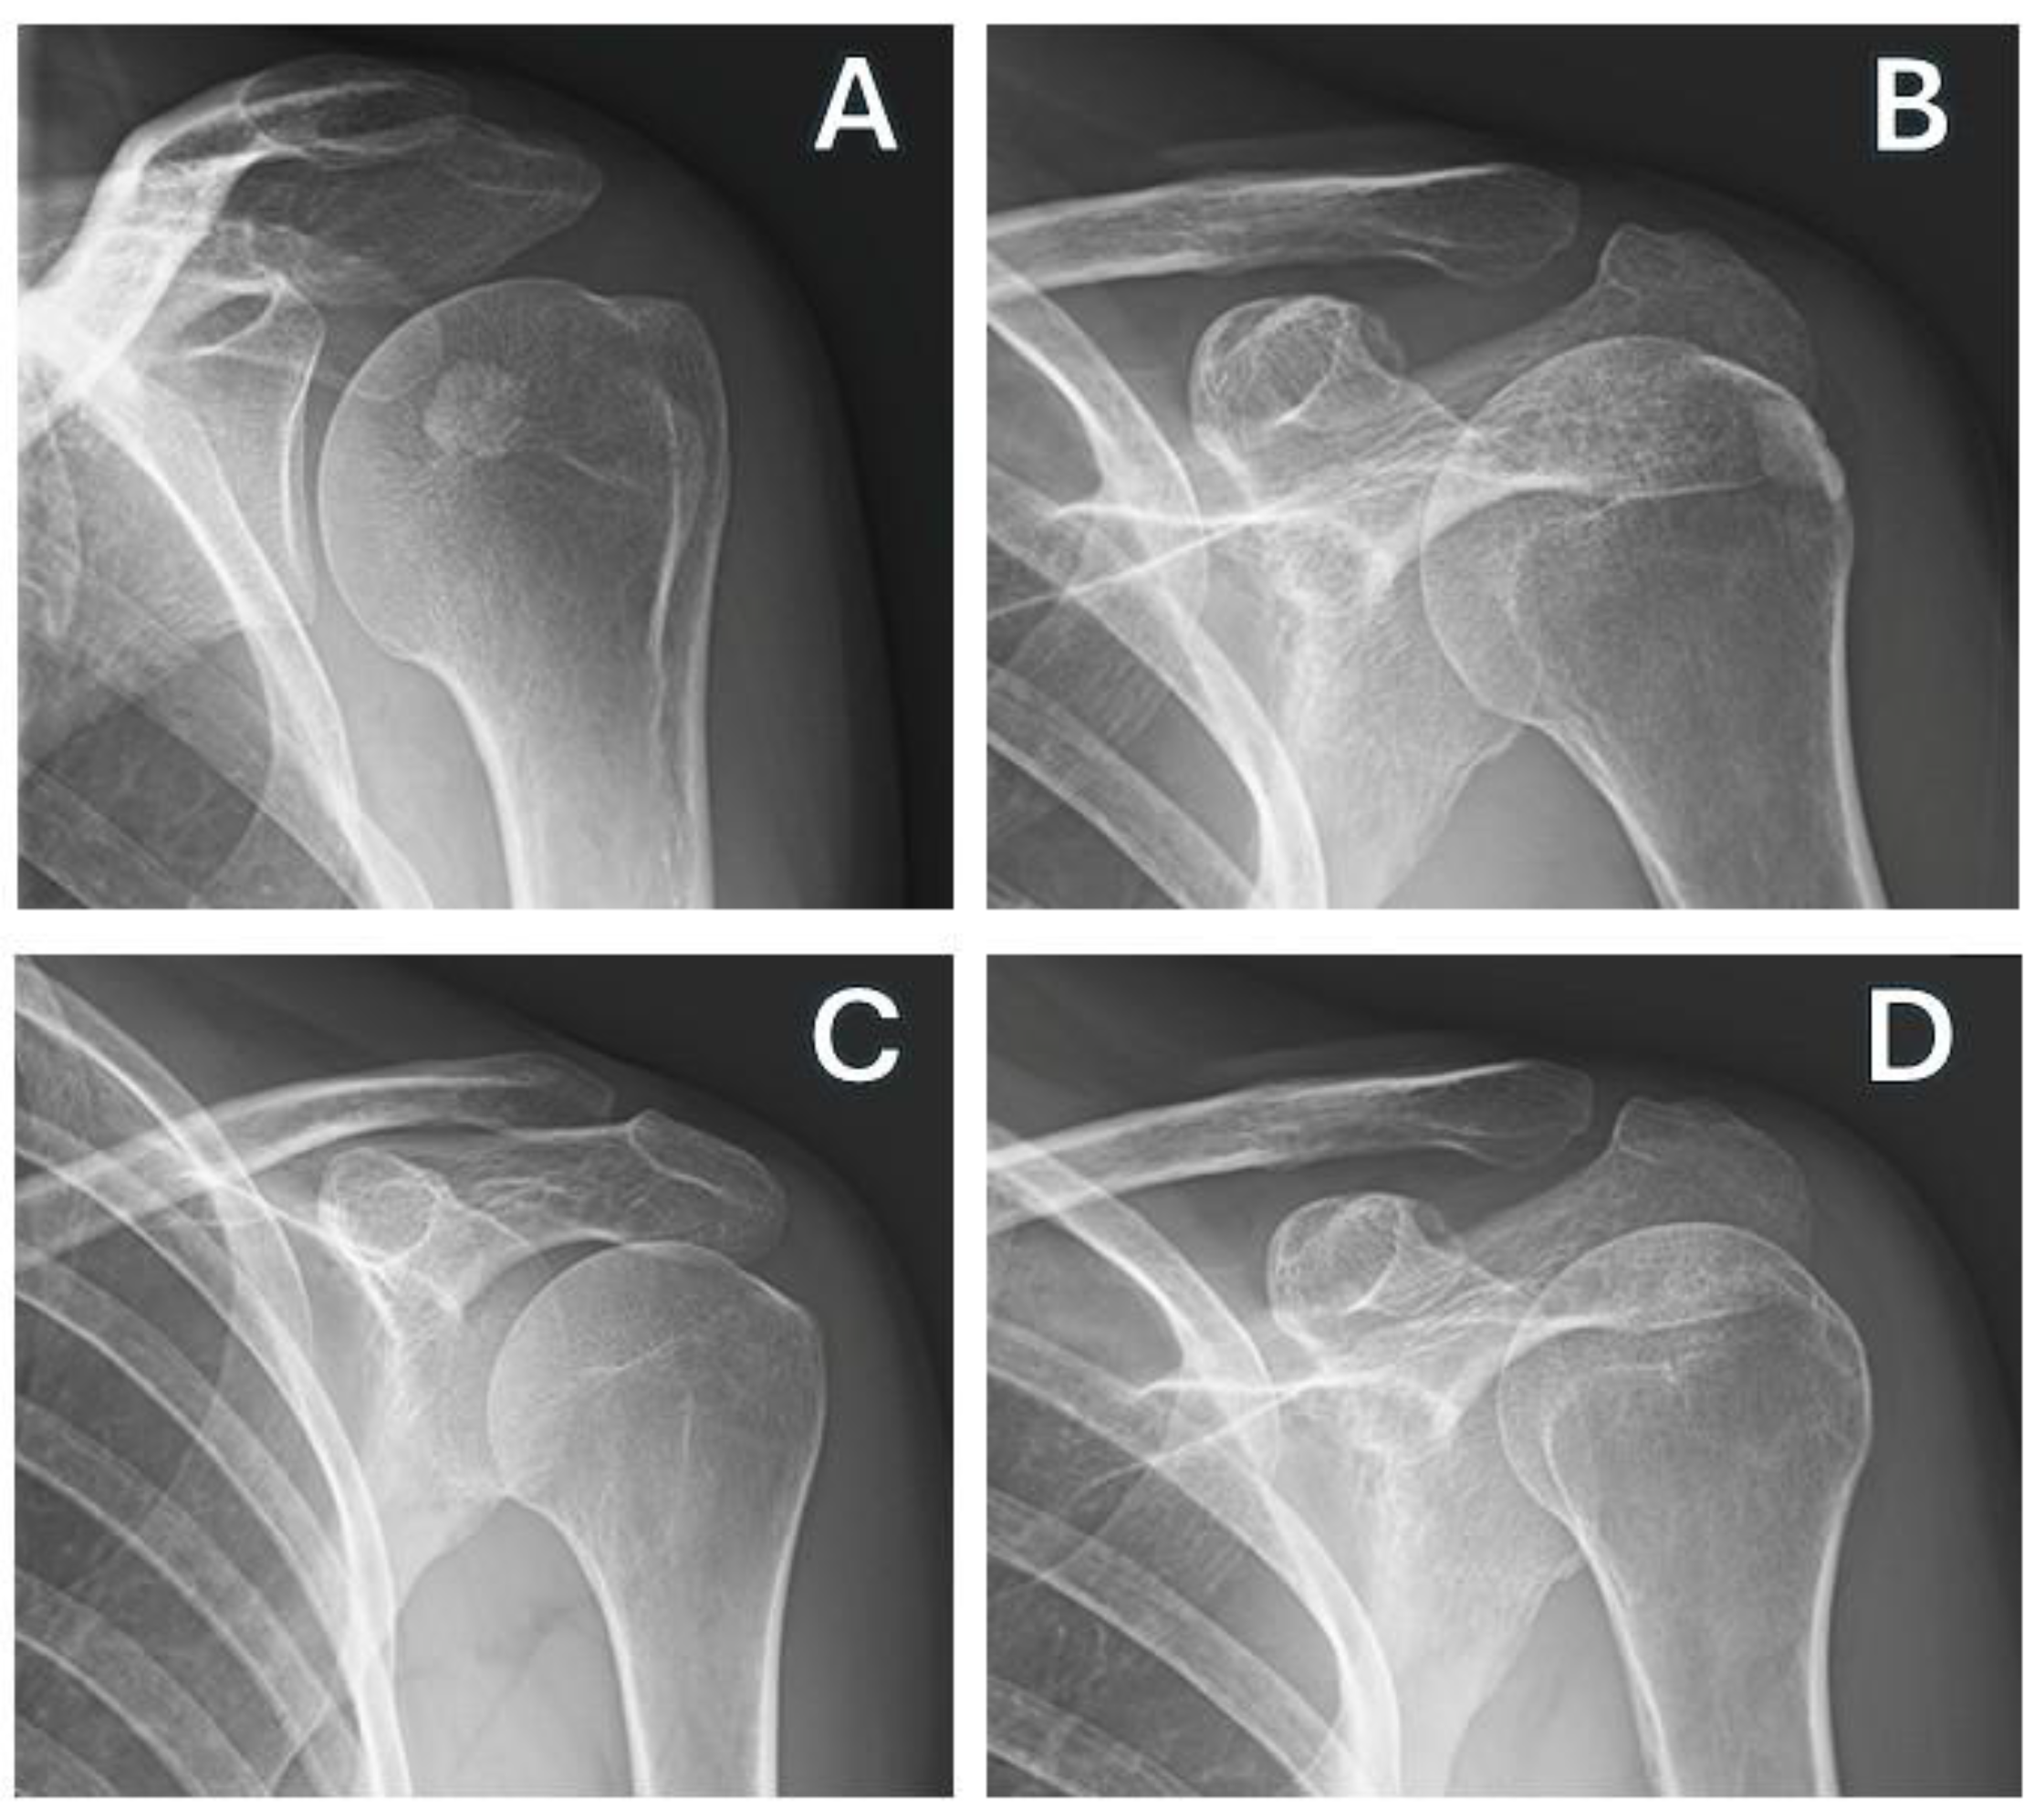

2.3. Outcome Measures

- Gartner, J.; Heyer, A. Calcifying Tendinitis of the Shoulder. Orthopade 1995, 24, 284–302. [Google Scholar]

| Gartner | 2 (1) | 3 (1) | 3 (0.5) | 0.004 * | −0.89 | −1.56 | −0.80 | 0.157 | −0.15 | −0.56 | 0.27 | <0.00001 * | 0.37 |